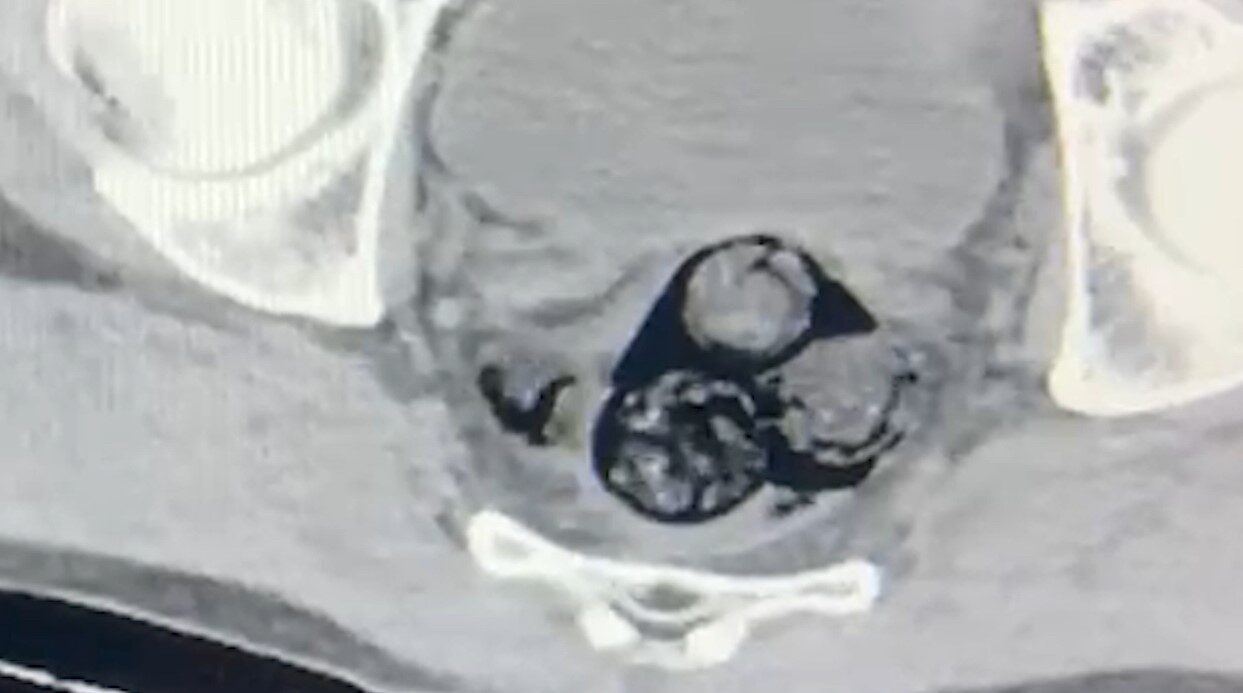

Iğdır İl Emniyet Müdürlüğü Narkotik Suçlarla Mücadele Şube Müdürlüğü ekipleri, yurt dışından Türkiye’ye giriş yapan ve şüpheli davranışlar sergileyen A.İ. isimli şahsı izlemeye aldı. Yapılan kapsamlı aramalar sonucunda, bu kişinin vücut boşluklarında uyuşturucu madde taşıdığı tespit edildi. Radyolojik inceleme, şüphelinin makat bölgesinde dört ayrı yabancı cisim olduğu bilgisini ortaya koydu.

Sağlık Kontrolü ve Uyuşturucu Miktarı

Şahıs, sağlık kontrolünden geçirilirken, çıkarılan cisimlerin içerisinde toplamda 140 gram metamfetamin bulunduğu belirlendi. Uyuşturucu madde taşımak ve ticaretini yapmak suçlamasıyla yargılanmak üzere A.İ., Iğdır Adliyesi’ne sevk edildi. Mahkeme karşısına çıkan olayın şüphelisi, tutuklanarak cezaevine gönderildi.